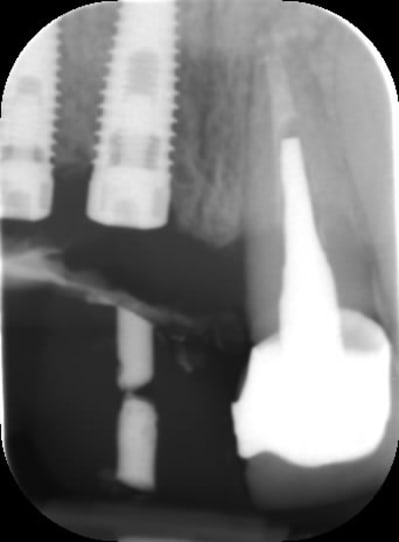

Bon voila le scann de 11-12 (pas 21-22 comme noté)

C'est vrai que j'ai à mort d'os en épaisseur.

Le manque est surtout en hauteur.

Dans tous les cas je refais 21 en même temps.

Tu ne ferais qu'un conjonctif enfoui ? Tu crois que c'est fiable dans le temps ?

j'ai l'impression qu'il ne manque pas d'os en verticale, ou à peine en 12.

Un bon cj avec un lambeau décalé en palatin ou en rouleau pour gagner en épaisseur me semblerai suffisant

le montage guide RX laisse supposer un manque d'un mm en 12 et ok en 11. Surcomble en cj pour en éliminer au cas où avant les empreintes